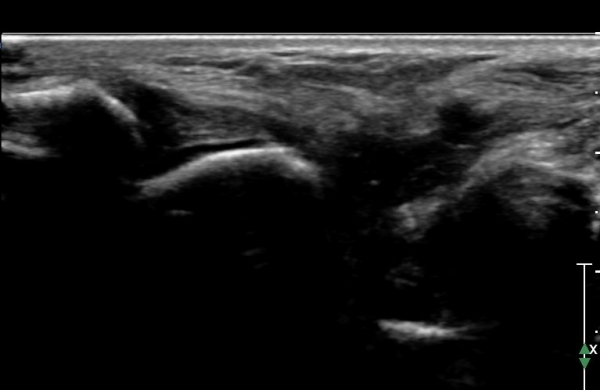

ÃÊÀ½ÆÄ °Ë»ç :  ¹ß¸ñ ¾ÕÂÊ Á¾´Ü¸é°Ë»ç¿¡¼­ ƯÀÌ ¼Ò°ß º¸ÀÌÁö ¾Ê´Â´Ù(»çÁø 1)